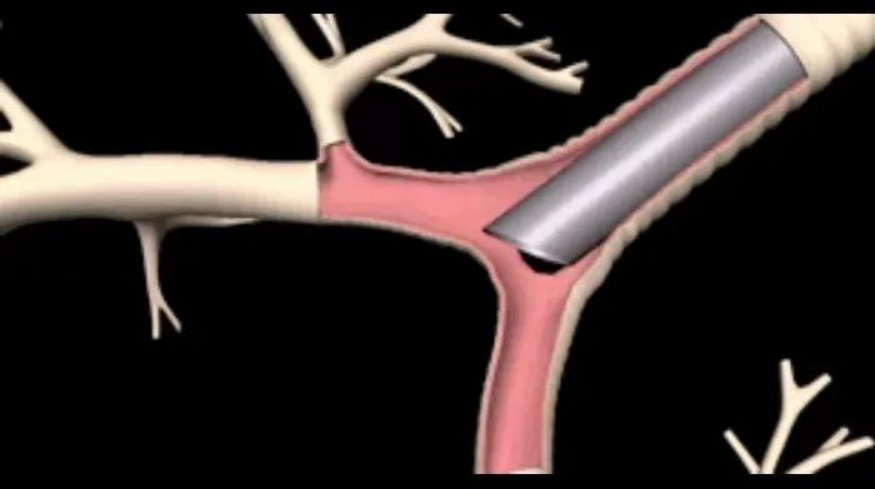

气道支架置入术是在支气管镜或X线的实时监视下,通过将管状的气管支架支撑物送入病变部(狭窄处),支架自展扩张,重建呼吸通道,缓解患者呼吸困难症状的一种气道介入技术。

根据材质不同,气道支架可分为金属支架和非金属支架2种。根据有无覆膜,金属支架又分为裸支架和覆膜支架,两种支架各有优缺点。覆膜支架有回收线,易取出且取出后支架多完整,但易潴留分泌物,直筒支架易移位。而裸支架易放难取,容易导致肉芽组织增生和再阻塞。根据临床需要,支架可制成直筒形(I形)、分叉形(L形和Y形)及特制形等。根据患者病变的部位来选择支架的形状,比如在气管内,可以选择直筒形(I形)支架,在隆突及左右主支气管的病变可以选择分叉形(L形和Y形)支架。